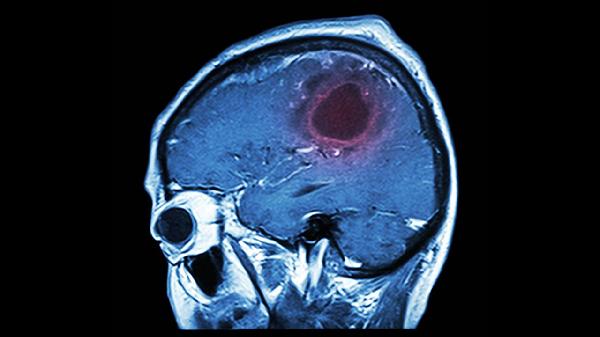

脑溢血是日常生活中比较常见的一种疾病,好发于老年人群居多,一般发病时间为冬季较多,出现脑溢血十分危害身体健康,甚至是危害到生命危险,而出现脑溢血会容易出现一些前兆,会容易导致四肢麻木,上肢没有力气,瘫痪等,会瞬间导致昏迷或者是摔倒。